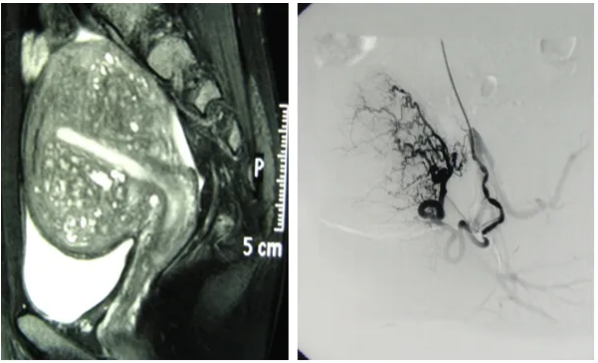

2. 精准导航:在数字减影血管造影(DSA)设备的实时引导下,将一根纤细柔软的导管,经血管系统精准送达子宫的供血动脉。

3. 靶向栓塞:通过导管,将大小适宜的栓塞颗粒注入目标血管。这个过程是可控且可视的。